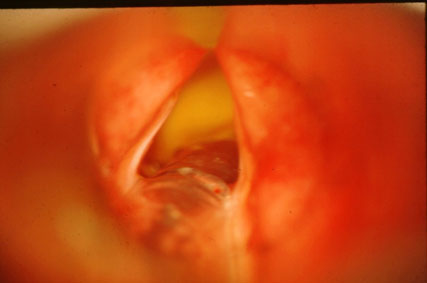

Anterior Cord Cancer

Post Laser Excision